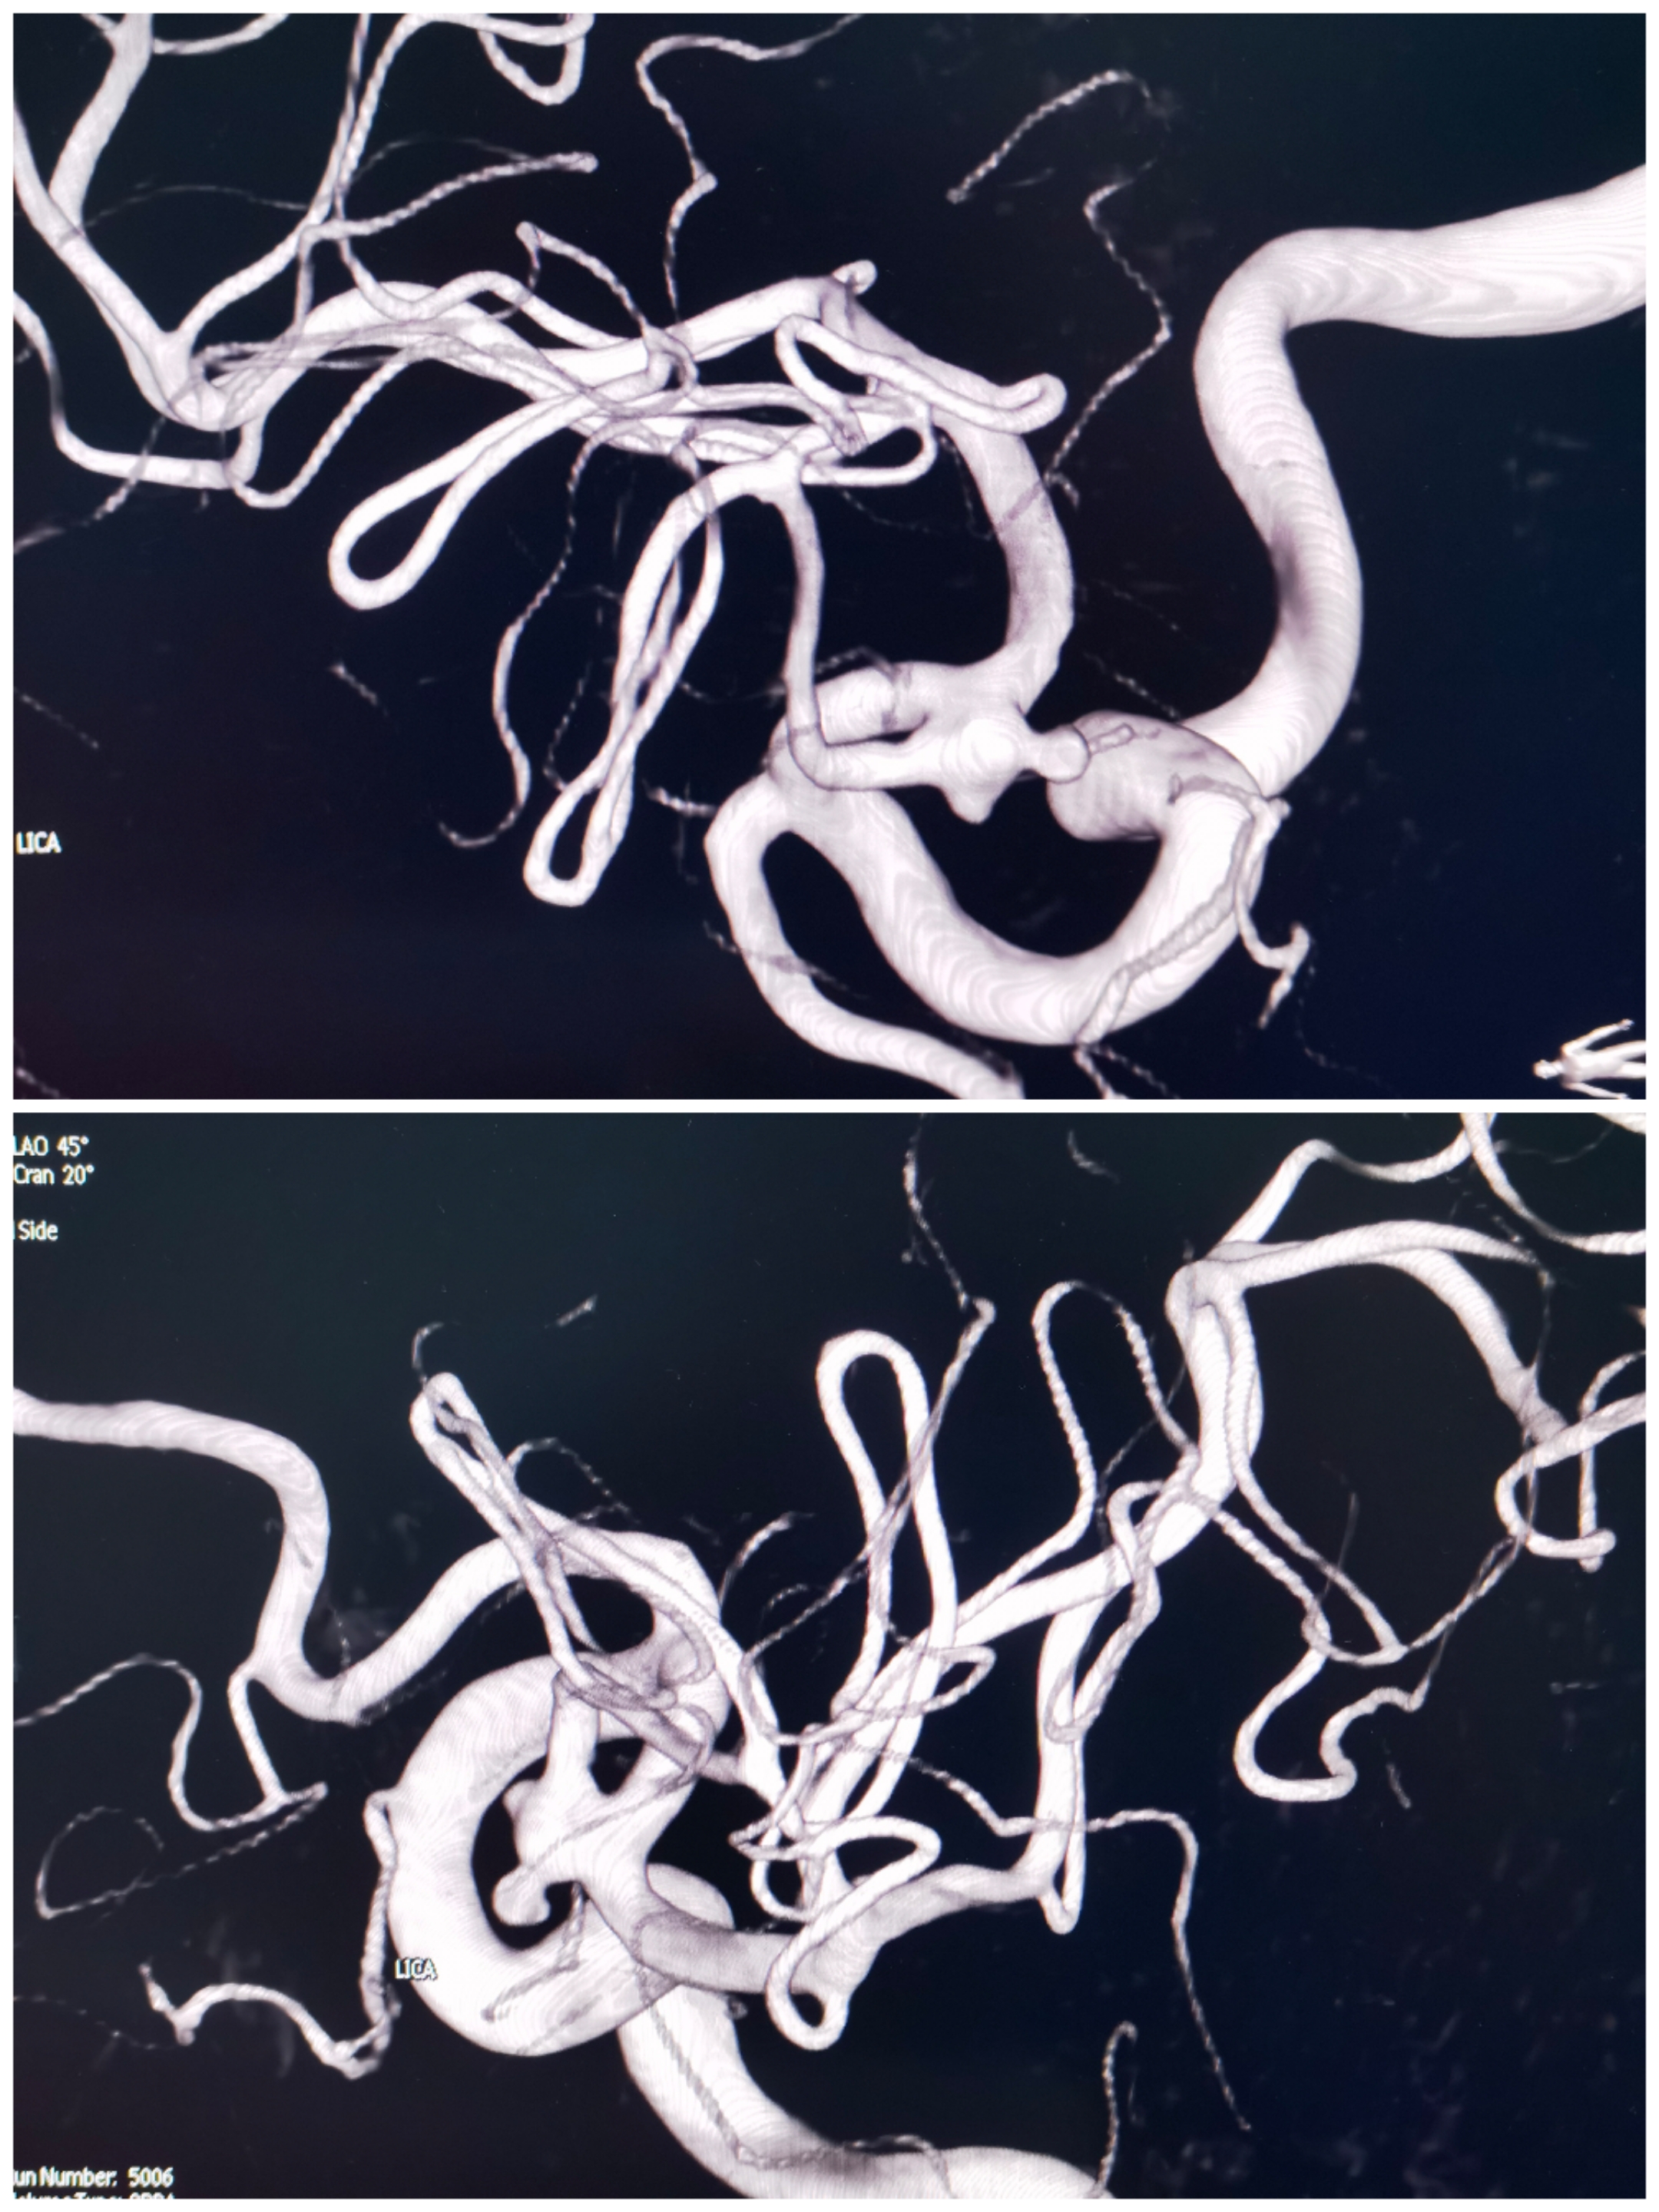

病例4后交通动脉瘤

患者因右侧眼睑下垂、动眼神经麻痹入院,CT无出血。

右侧颈内造影提示后交通不规则动脉瘤

椎动脉造影提示右侧P1良好,无需刻意保留后交通动脉

3D重建情况

拟支架辅助+双微管栓塞,微导管布局情况

先栓塞远端子囊+支架释放,双微管交替栓塞

栓塞术后情况